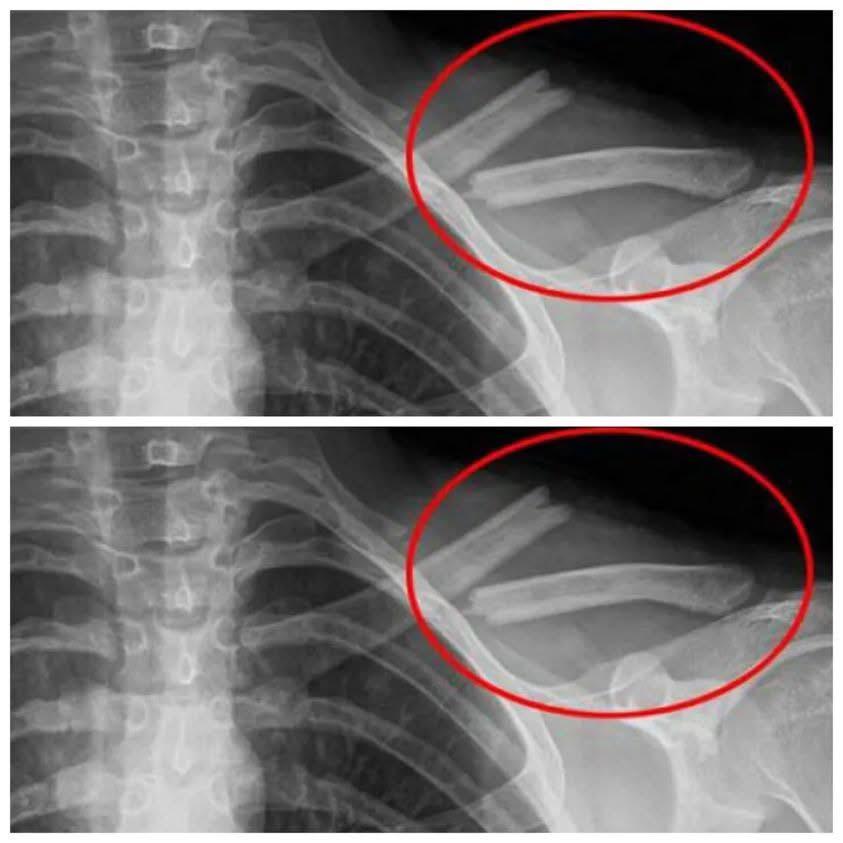

7. Soft Drinks + Soft Bones + Osteoporosis

If you don’t want to have to depend on calcium supplements all your life, regulate your soda intake immediately. It greatly weakens the basic skeleton that our form depends on, leading to a lot of joint pain and other detrimental health damages.